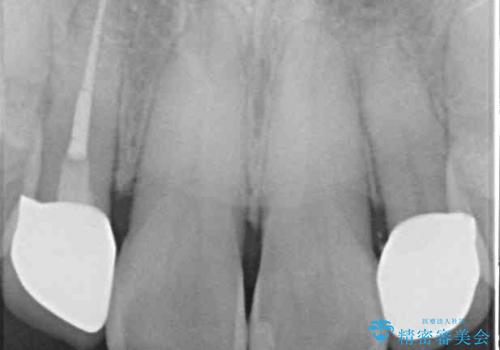

矮小歯であった上顎前歯2本は、矯正治療後にバランスの取れた大きさのオールセラミッククラウンを装着しました。